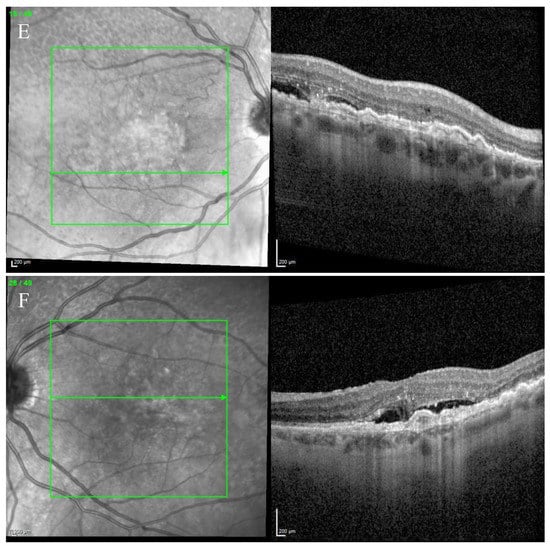

Fundus examination showed a macular yellowish elevated lesion in both eyes (Figure 6A,B). FAF revealed a hypoautofluorescent macular lesion (Figure 6C,D).

Figure 6.

Case 5. Multimodal imaging features of bacillary layer detachment (BALAD) in neovascular age-related macular degeneration patients in both eyes. (A,B) Optos Ultra-widefield colour shows a macular yellowish slightly elevated macular lesion. (C,D): Optos Ultra-widefield autofluorescence imaging shows a hypoautofluorescent macular lesion. (E) Heidelberg Spectralis optical coherence tomography shows a type 1 MNV with subretinal and intraretinal fluid and BALAD in the right eye. (F) Heidelberg Spectralis optical coherence tomography shows a type 1 MNV with subretinal fluid and BALAD in the left eye.

The OCT showed a type 1 MNV with a fibrovascular PED, subretinal fluid, and BALAD in both eyes (Figure 6E,F).

The OCTA scan confirmed the presence of MNV (Figure 7A,B).

Over the years, these features have shown improvement phases alternating to worsening ones.

The patient is still on treatment with anti-VEGF intravitreal injections (T&E regimen) for both eyes.

The BCVA has been stable throughout the treatment period. When last examined, it was 0.63 logMAR in the right eye and 0.32 logMAR in the left eye.